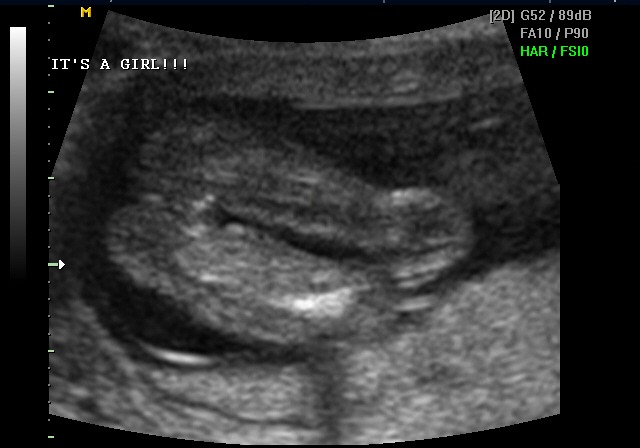

Yesterday we went into the Perinatologist to have a level two ultrasound performed. The tech was very nervous and was unsure about a few things. I was sure what was wrong after about ten minutes. When the tech left the room I mentioned it lightly to Bertha and we waited for the doctor to return.

He returned with the worst news I have ever heard in my life. Kennedy had multiple problems. A genetic defect. Spina bifida. A cyst on the brain. Clenched fists. Clubbed foot. The banana sign. A heart defect. They asked us to perform an amniocentesis, which we did.

The ultrasound didn't show any new problems. Kennedy was now one pound, fourteen ounces. A little small, but still where we should expect. The doctor was much nicer this time — actually telling us she expected us to go to term. She mentioned we should expect a short lifespan, but other than that, it was positive.